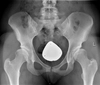

Düşme Sonucu Kalça Kırığı Riski Nasıl Azaltılır?Düşme, özellikle yaşlı bireylerde kalça kırıkları gibi ciddi yaralanmalara yol açabilen önemli bir sağlık sorunudur. Bu makalede, düşme sonucu kalça kırığı riskini azaltma yöntemleri üzerinde durulacaktır. Düşme Nedenleri ve Risk FaktörleriDüşme olayları, çeşitli faktörlerin birleşimi sonucunda gerçekleşir. Bu faktörler arasında;

SonuçDüşme sonucu kalça kırığı riski, yaşlı bireylerde önemli bir sağlık sorunu oluşturmaktadır. Ancak, yukarıda belirtilen önlemler ve stratejilerle bu risk önemli ölçüde azaltılabilir. Denge ve kuvvet artırıcı egzersizler, düzenli sağlık kontrolleri, çevresel düzenlemeler ve sağlıklı beslenme alışkanlıkları, bireylerin bu riski minimize etmelerine yardımcı olacaktır. Toplum genelinde bilinçlendirme çalışmaları da bu konuda kritik bir öneme sahiptir. |